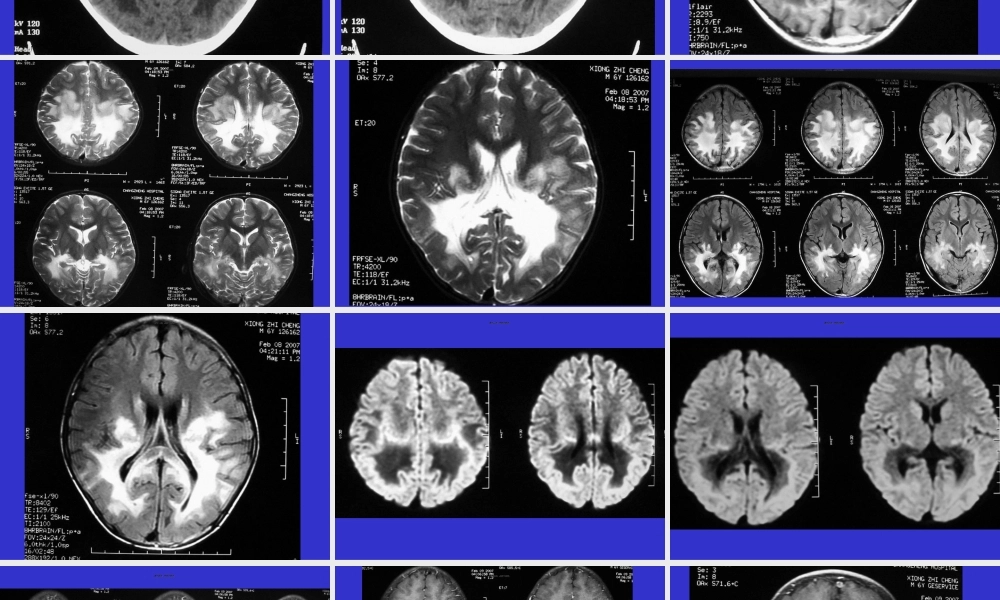

常见(chánjiàn)ɡ脑白质病梅河口市新华医院第一页,共四十四页。第一页,共四十四页。第二页,共四十四页。第二页,共四十四页。第三页,共四十四页。第三页,共四十四页。第四页,共四十四页。第四页,共四十四页。第五页,共四十四页。第五页,共四十四页。第六页,共四十四页。第六页,共四十四页。第七页,共四十四页。第七页,共四十四页。第八页,共四十四页。第八页,共四十四页。第九页,共四十四页。第九页,共四十四页。第十页,共四十四页。第十页,共四十四页。第十一页,共四十四页。第十一页,共四十四页。第十二页,共四十四页。第十二页,共四十四页。第十三页,共四十四页。第十三页,共四十四页。第十四页,共四十四页。第十四页,共四十四页。第十五页,共四十四页。第十五页,共四十四页。第十六页,共四十四页。第十六页,共四十四页。第十七页,共四十四页。第十七页,共四十四页。第十八页,共四十四页。第十八页,共四十四页。第十九页,共四十四页。第十九页,共四十四页。诊断(zhěnduàn):肾上腺脑白质营养不良肾上腺脑白质营养不良(Adrenoleukodystrophy,ALD),又称阿狄森-弥漫性脑硬化症(Addison-SchilderDisease)、黑皮脑白质营养不良、……等、1912年Schilder首次报道,Blaw于1964年正式命名为肾上腺脑白质营养不良。该病是脑白质营养不良中最常见的一种,通常是指一组X染色体连锁(liánsuǒ)隐性遗传的疾病(简称X-ALD),但广义上也包括一组常染色体隐性遗传的ALD(简称为A-ALD,automosalALD),即指新生儿ALD。第二十页,共四十四页。第二十页,共四十四页。病理(bìnglǐ)•目前一般认为由于溶酶体过氧化酶的缺乏,导致极长链脂肪酸在细胞异常堆积,特别在脑白质和肾上腺皮质内的沉积、导致脑白质和肾上腺皮质的破坏,从而产生特征性的脑白质和肾上腺皮质损害的临床(línchuánɡ)症状。第二十一页,共四十四页。第二十一页,共四十四页。脑皮质厚度稍薄或正常。主要病理改变在白质,呈弥漫性白质减少致脑室(nǎoshì)中、重度扩大、脑沟增宽。顶、枕、颞叶等处脑向质内出现对称性髓鞘脱失改变、可有显著胶质增生。病变常侵及胼胝体,主要在压部。额叶的脱髓鞘发生稍迟且多不对称。小脑、脑干也可以有脱髓鞘发生,内囊、外囊、锥体束等可见连续性髓鞘脱失改变。並可出现鈣质沆积,有时很广泛而显著。第二十二页,共四十四页。第二十二页,共四十四页。这些髓鞘脱失区从外向内可分为三个病理(bìnglǐ)...